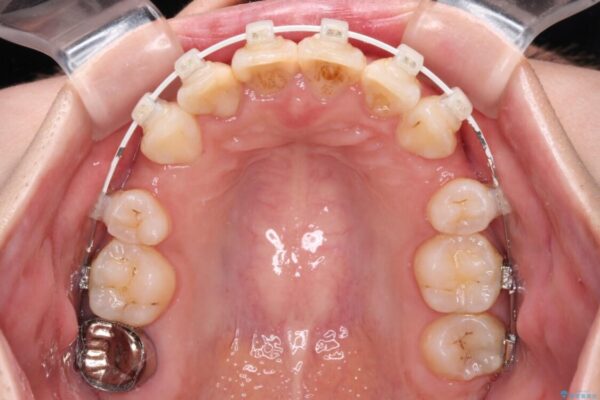

治療途中

• デコボコと深い咬み合わせ ワイヤー装置での抜歯矯正 治療途中画像

下顎の叢生を解消するために抜歯が必要であり、奥歯の咬み合わせや口元の印象から、上顎も同様に抜歯と判断し、上下左右の第1小臼歯4本抜歯してワイヤー装置にて矯正治療を行うこととしました。

咬み合わせが深く、そのままでは上顎の抜歯スペースが閉じきらない可能性があったため、治療初期から深い咬み合わせを改善させるように試みました。

実際にはなかなか改善されず、当初予定よりも治療期間がやや長期化してしまいました。